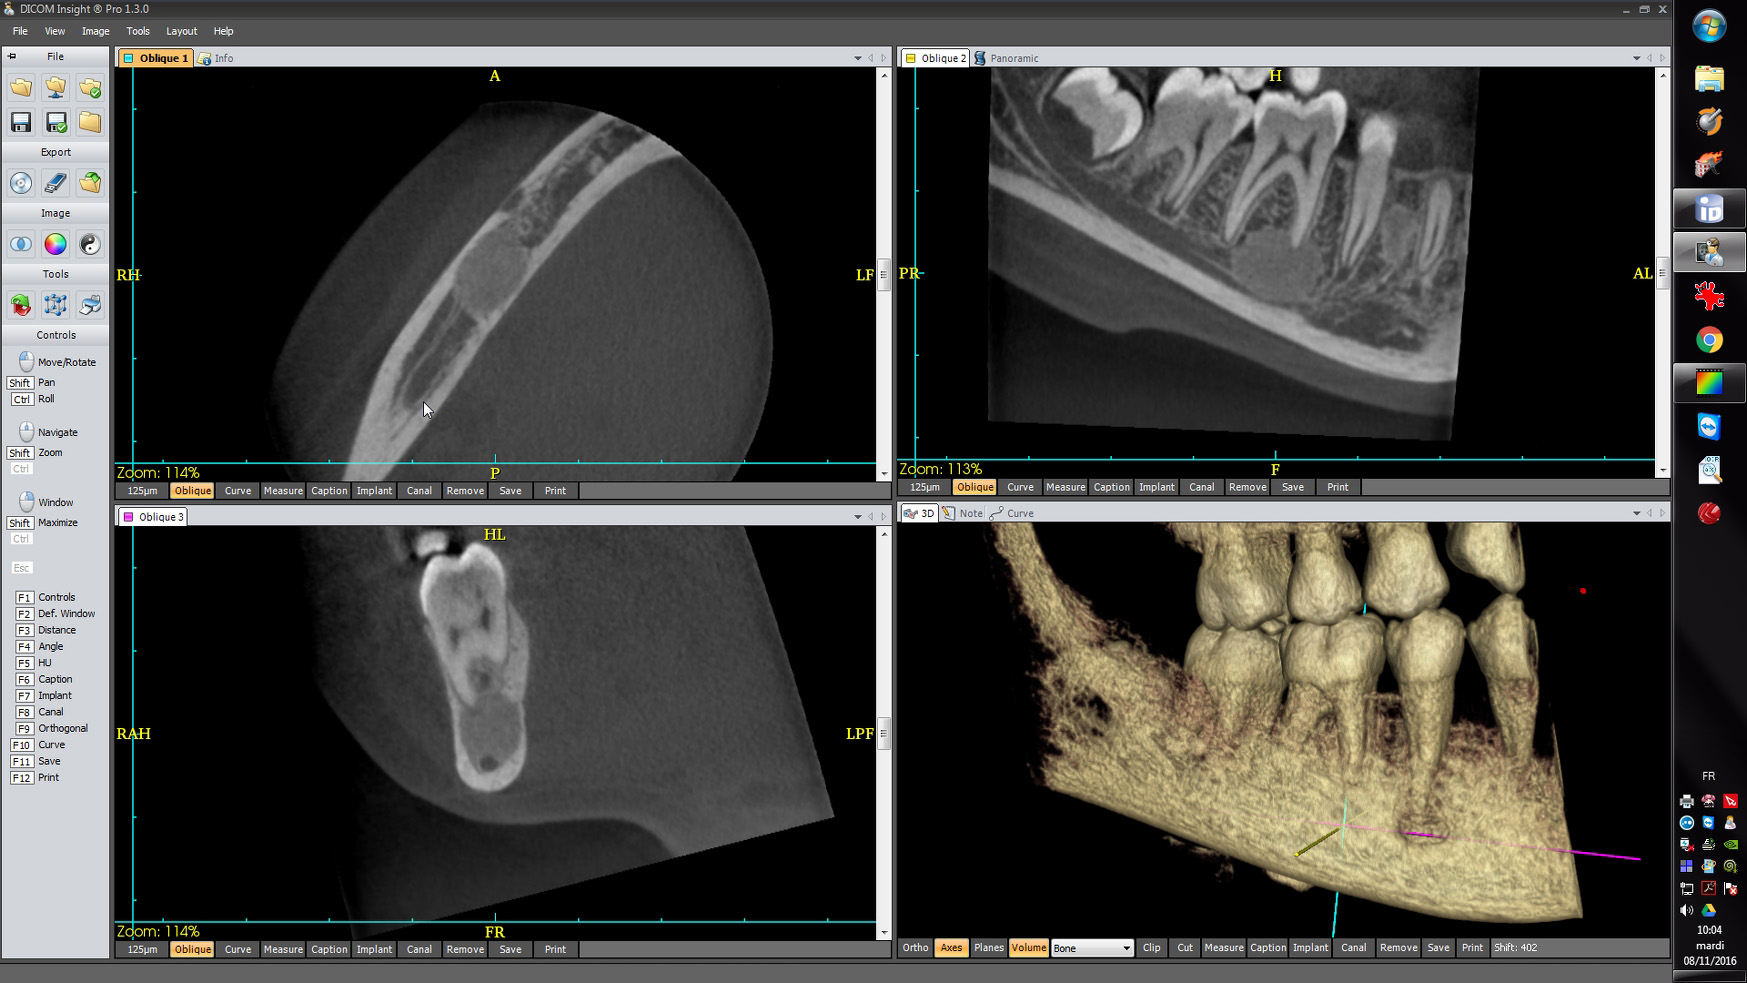

CBCT :

A. Observez sur les reconstructions axiale et panoramique les lésions apicales de :

C. Le diagnostic est : Dysplasie osseuse (anciennement cémento-osseuse) floride.

L’attitude à adopter est l’abstention thérapeutique. Les dents sont vivantes et doivent être considérées comme des dents saines, sauf complications infectieuses, comme pour tout patient.

DISCUSSION : LES DYPLASIES OSSEUSES ou DYSPLASIES CEMENTO-OSSEUSES

Affections congénitales caractérisées par la production accrue de cément réalisant des lésions cémento-osseuses apicales non tumorales. Leur traitement est le plus conservateur possible et l’intervention réservée aux cas compliqués et/ou symptomatiques.

Leurs trois formes sont probablement les variantes d’un même processus lésionnel.

B. La dysplasie osseuse (ou cémento-osseuse) floride (Fig.4). Elle touche surtout la femme noire d’âge moyen, affectant les deux maxillaires de façon plus ou moins diffuse et symétrique, associant des lésions de grande taille à tous les stades, pouvant s’infecter et se compliquer d’ostéite.